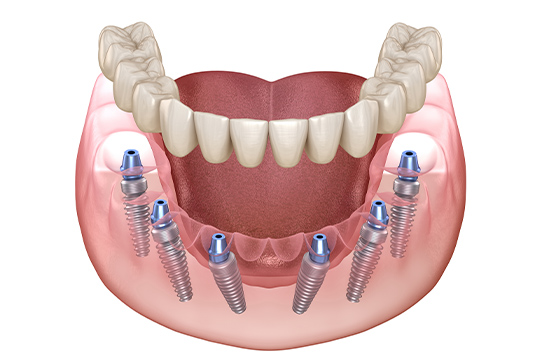

전악 임플란트는 임플란트 틀니보다 씹는 힘이 훨씬 좋습니다.

내 치아처럼 사용이 가능하며

전체 치아 기능의 90% 정도로 회복력이 좋습니다.

구강 상태와 잇몸 뼈를 정밀하게 진단한 후

개인에게 맞는 계획으로 임플란트를 식립합니다.